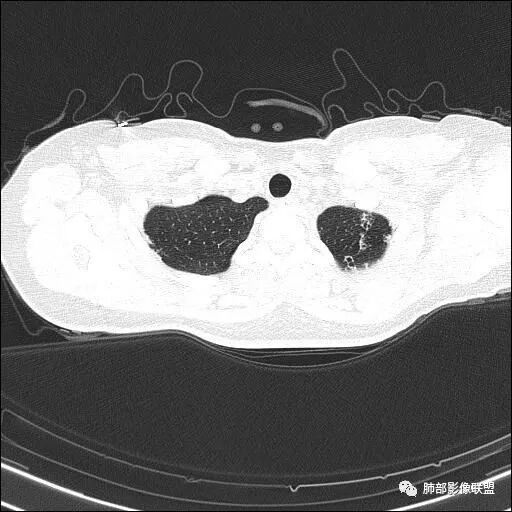

【每日晨读】双肺上叶多发薄壁空洞

两肺多发病灶

分布特点:上肺胸膜下

2.双肺多发薄壁空洞影、条索影及结节影,边界较清楚,密度偏高不柔和,散乱,但有成簇倾向或堆积感,胸膜下分布为主,双肺上叶分布为主。

3.空洞相当不规则,缺乏张力,未见血管穿行,未见壁结节,未见液平。

4.双肺门及纵隔未见肿大淋巴结。未见胸腔积液。